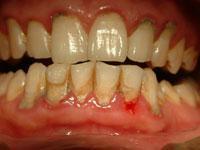

牙齦炎階段:牙齦紅腫出血,牙齒周圍有牙石

早期牙周炎:除牙齦炎癥外,牙周袋形成,牙槽骨輕度吸收